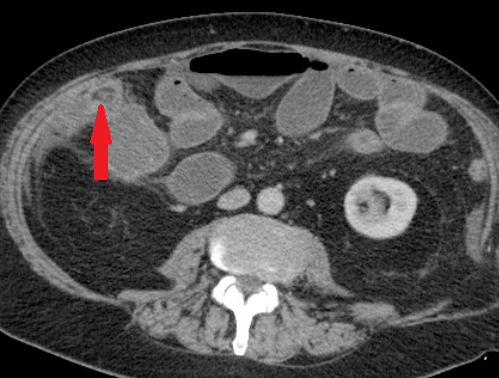

Σχήμα 1 . Η αξονική τομογραφία με ενισχυμένη με σκιαγραφικό έδειξε μια ακανόνιστη περιφερική μάζα στο αριστερό μισό του εγκάρσιου κόλου με λιπώδη συσσωμάτωση δίπλα σε παχυσμένο τοίχωμα του εντέρου. ( Ευγενική παραχώρηση Δρ. Β. Πενόπουλος ) .